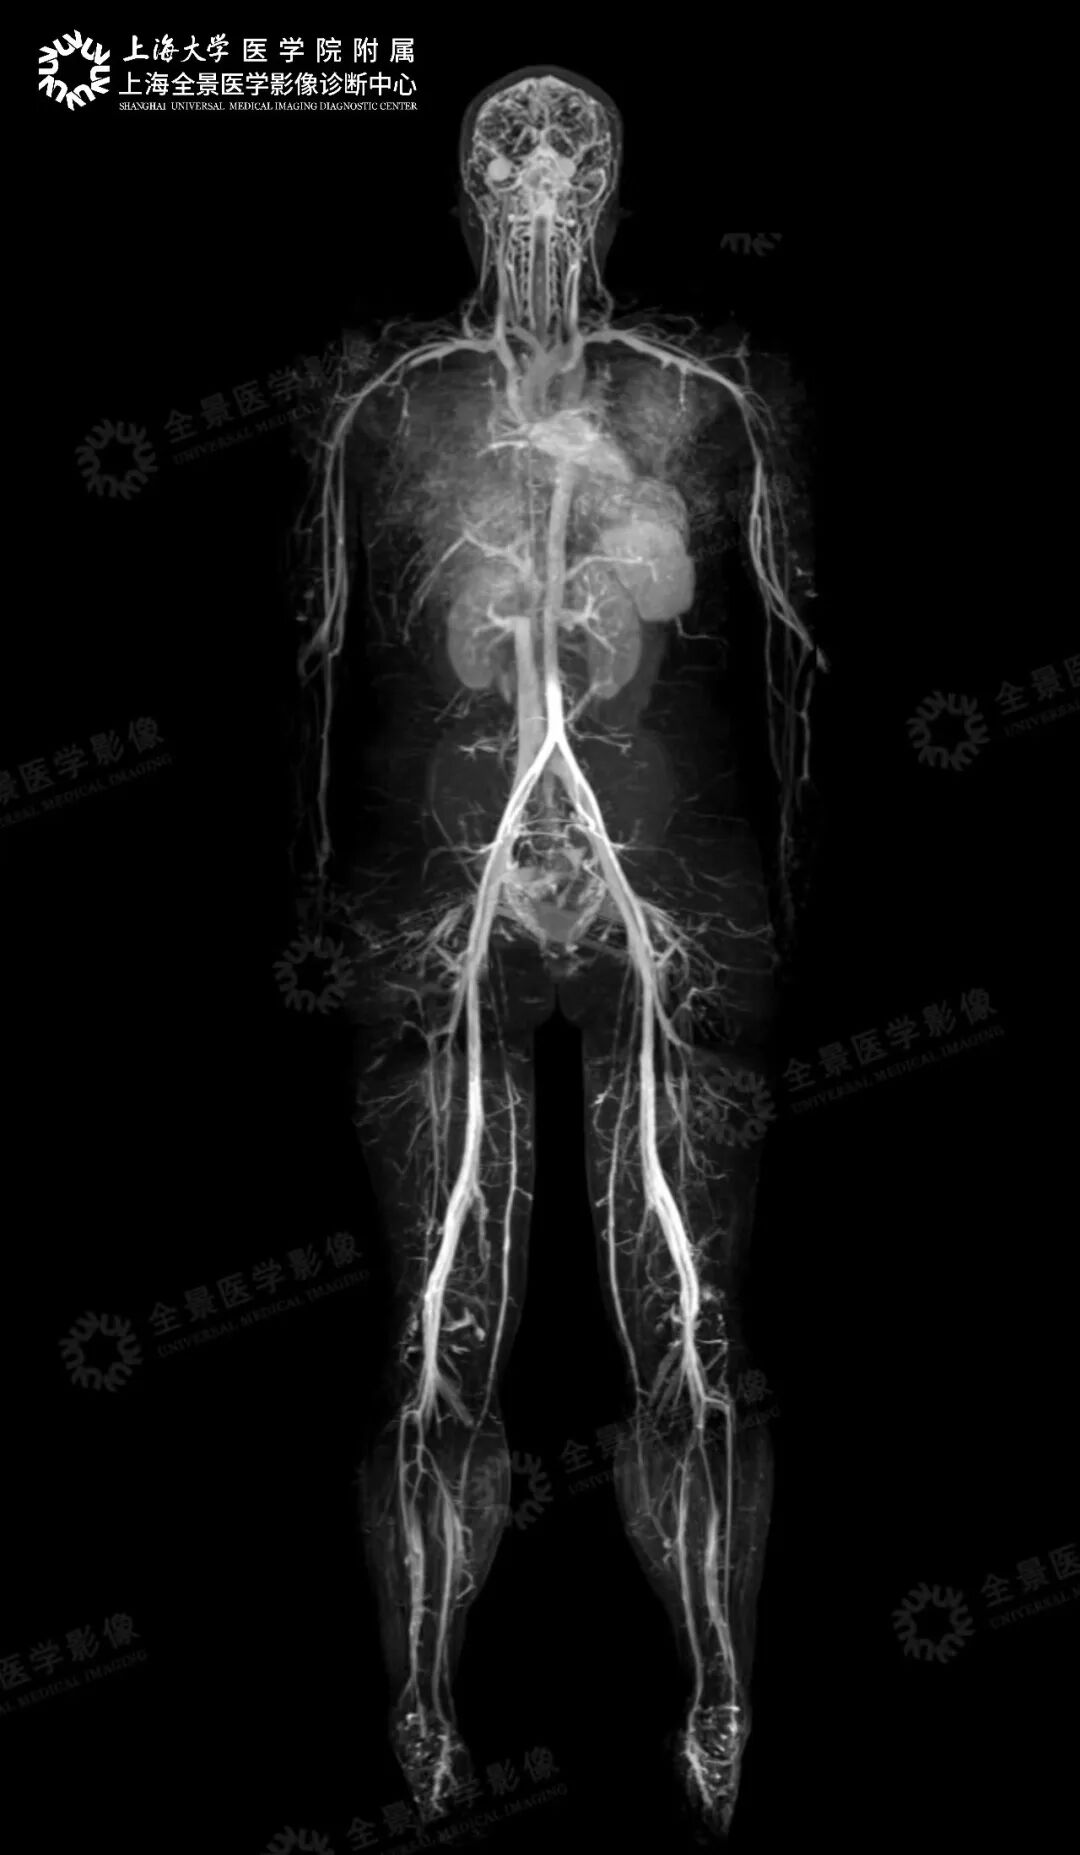

血管疾病风险评估:【头颈心 CTA 联合扫描】, 用于心脑核心血管筛查,对于发现早期心脑血管疾病尤为重要!【磁共振全身血管成像】 一次扫描,能同时获得脑动脉、颈动脉、冠状动脉、肺动脉、胸主动脉、腹主动脉、肾动脉以及下肢血管图像。